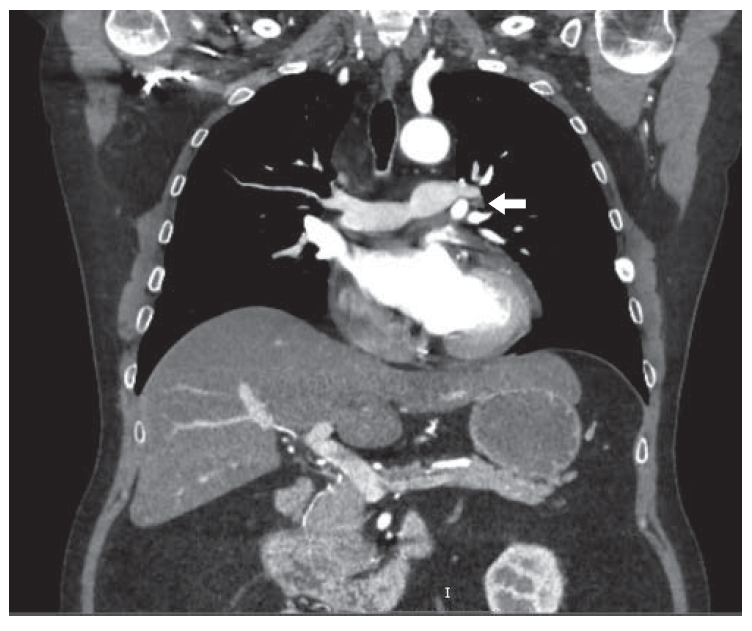

Таким образом, тактика ведения пациента Б. по результатам селективного забора крови из НКС радикально изменилась: рекомендованное ранее радиохирургическое лечение отменено, инициирован поиск нейроэндокринной опухоли. По данным проведенной МСКТ органов грудной клетки, брюшной полости и забрюшинного пространства с контрастным усилением, в прикорневой зоне левого легкого, по заднему контуру левой верхней легочной вены, медиально от верхнедолевого бронха и кпереди от левой ветви легочной артерии определяется мягкотканный участок размерами 8 × 6 мм, активно накапливающий контрастный препарат (рис. 2). Плотность данного участка в разные фазы (нативная, артериальная, венозная) составляет соответственно 20–117–92 ед.Н. По заключению специалиста МСКТ, образование в прикорневой зоне левого легкого с учетом характера контрастирования не позволяет полностью исключить АКТГ-эктопию, образование необходимо дифференцировать с бронхопульмональным лимфатическим узлом. При дальнейшем обследовании не удалось выявить иной очаг возможной эктопической продукции АКТГ. Учитывая умеренный характер гиперкортицизма и стабильное состояние пациента, было рекомендовано проведение дообследования с целью уточнения источника гиперпродукции АКТГ: проведение ПЭТ-КТ с определением дальнейшей тактики ведения. На проведенной в апреле 2018 г. ПЭТ-КТ с 68Ga-(DOTA)-TATE отмечены признаки гиперплазии левого надпочечника, SSТR-позитивной опухолевой ткани не выявлено. Единичные плотные очаги в обоих легких (вероятно,поствоспалительного генеза). Продолжается лечение октреотидом пролонгированного действия как пациенту с предполагаемой нейроэндокринной опухолью. На этом фоне в анализах, сделанных по месту жительства утром через 4 дня после введения пролонгированного октреотида: АКТГ 71 пг/мл (норма до 46), кортизол 24,6 мг/дл (норма до 25), гликемия натощак в пределах референсных значений, артериальное давление на гипотензивной терапии 140/90 мм рт.ст. Продолжается динамическое наблюдение, планируется дальнейший поиск источника АКТГ-эктопии (КТ органов грудной клетки, брюшной полости через 6 мес).

3. Рис. 2. Компьютерная томограмма органов грудной клетки с контрастным усилением пациента Б. В прикорневой зоне слева, по заднему контуру левой верхней легочной вены, медиально от верхнедолевого бронха и кпереди от левой ветви легочной артерии определяется овальной формы мягкотканная структура размерами 8 × 6 мм, активно накапливающая контрастный препарат. | |